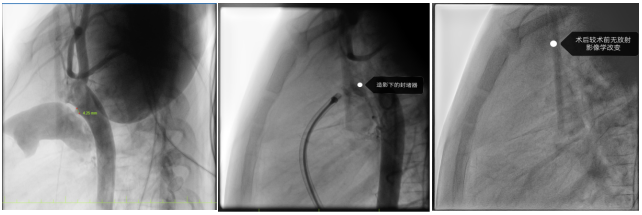

在张智伟教授指导下,玉溪市人民医院心内科团队手术过程中,精准定位动脉导管分流位置,将生物可降解封堵器成功植入,实现了对分流的有效封堵。术后超声评估封堵器周围无残余分流,封堵器占位良好。